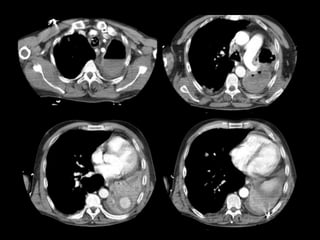

• Otro caso

Varón de 56 años que consulta por hemoptisis